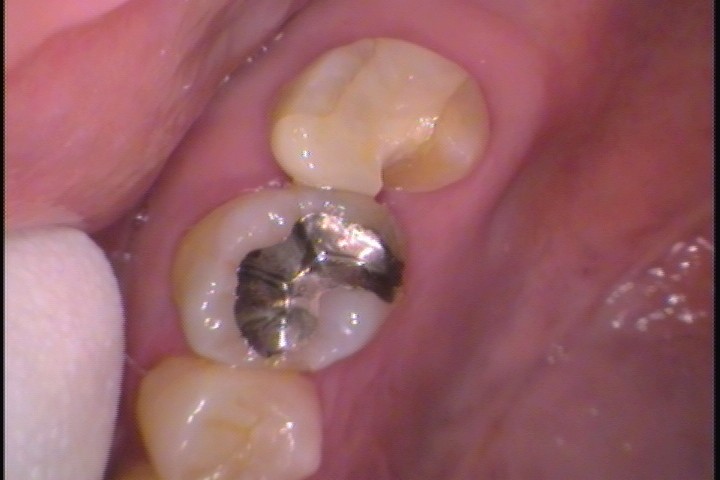

現在は使われないアマルガム

過去に保険適応され、虫歯の治療で主に使われていた金属材料に「アマルガム」というものがあります。

金属材料から耐久性があり、さらに抗菌性を有し虫歯になりにくい特徴があります。中高年のお口の中には現在も存在する詰め物です。つまり長い年月持っている材料ということです。

2000年に入り国内ではアマルガムの製造は中止され、現在一般的に使われることはほとんどありません。

アマルガムが充填されている歯

パラジウム合金と違い、光沢の無い銀歯。アマルガムの成分で歯が黒く変色している場合が多い。

「アマルガム=体に悪いもの」というネット記事が多く書かれているが、既にお口の中にあるアマルガムについては問題ありません。学会でも安全性に関して発表していますので、こちらをご覧ください☟